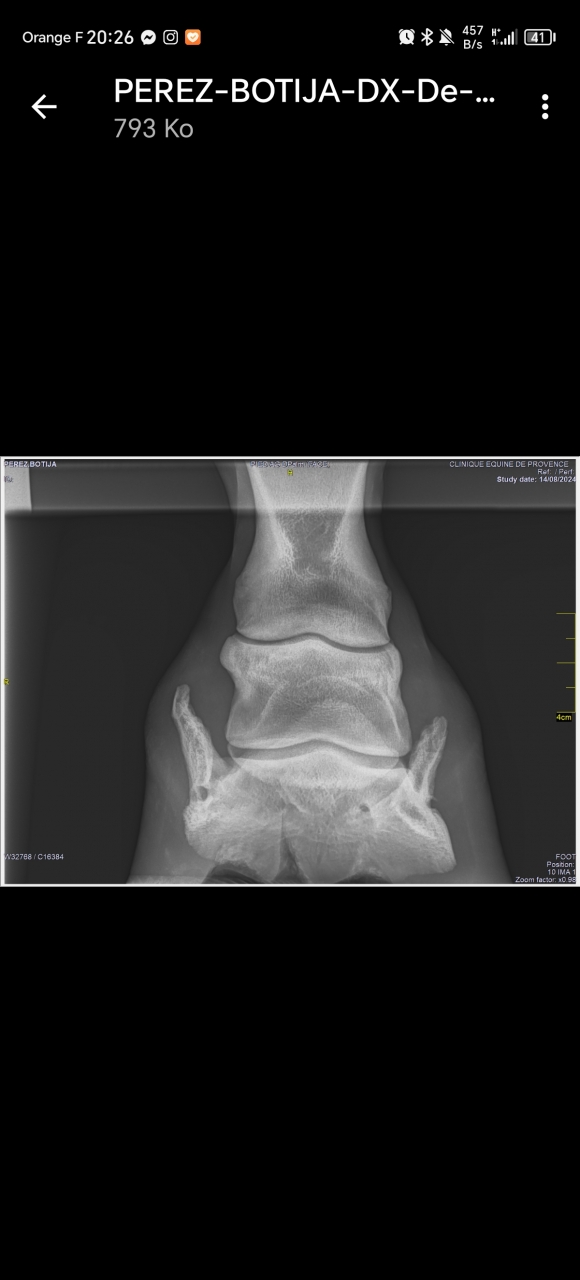

| Dire merci | bon alors... Evidemment le fer génait ce qu'on voit à la radio c'est que le haut jusqu'à la moitié de la "corne" s'opacifie et a moins cet aspect mité donc c'est positif. En revanche on voyait pas le trait de fracture avec le fer mais à la palpation elle a mal (juste au dessus de la couronne).La ferrure est ok, on l'enlève dans 6 semaines, on refait RX et on voit ce qu'on fait. Donc, ça avance, ça nous emmerdera toute notre vie (ça c'est ma compréhension et mon feeling). La véto m'a dit qu'il fallait qu'elle évite absolument de trotter... je vais devoir fermer le paddock plus petit ![]() Bref, ça c'était avant : Lien ![]() [url=https://ibb.co/J5Tm7xz][img]https://i.ibb.co/SRg5nQK/PEREZ-BOTIJA-DX-De-14-08-2024-S4-I0.png" alt="" /> https://ibb.co/7tLbYCq Message édité le 20/09/24 à 13:55 Message édité le 20/09/24 à 13:57 |

| Dire merci | En vrai je suis assez fataliste. Si ça gaze ça gaze et si ça va pas a la monte bah ... Je la monterai pas ... Je vais pas la vendre de toute façon, c'est pas le genre de la maison ![]() Mais bon on en est pas là. ![]() Pour comparer gauche droite ![]() Là ce qui s'est opacifié c'est plutôt la pointe de la calcification, faut donc être patient pour le reste. |